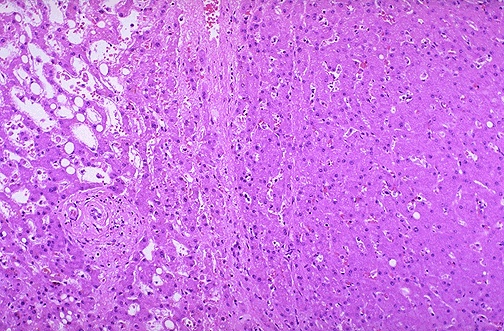

| Normal liver tissue with a portal tract is seen on the left. The hepatic adenoma is on the right and is composed of cells that closely resemble normal hepatocytes, but the neoplastic liver tissue is composed of disorganized hepatocyte cords and does not have a normal lobular architecture. |